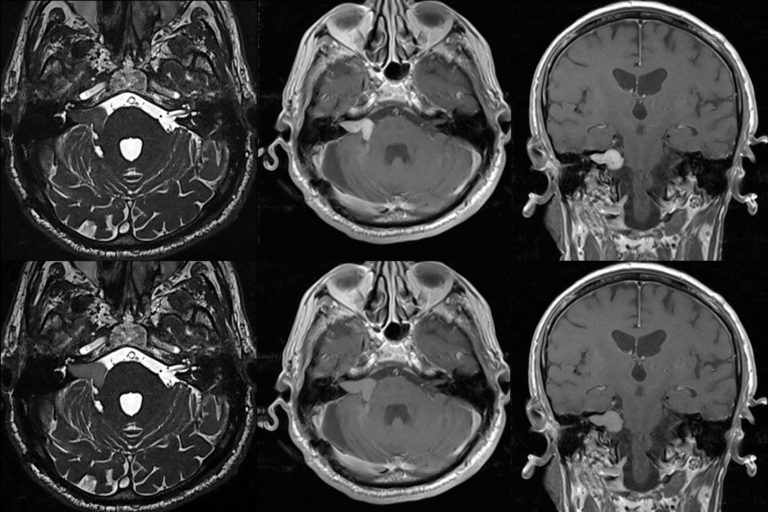

Akustikusneurinom

Ein Akustikusneurinom ist ein seltener, gutartiger Tumor, der am Nervus vestibulocochlearis entsteht, der das Innenohr mit dem Gehirn verbindet. Dieser Tumor tritt am häufigsten bei Menschen im Alter von 30 bis 60 Jahren auf, kann aber in jedem Alter vorkommen. Er wächst in der Regel langsam, wobei ein einseitiger Hörverlust oft das erste Symptom ist. Weitere Symptome können Tinnitus, Gleichgewichtsstörungen und Schwindelanfälle sein. Behandlungsmöglichkeiten umfassen die Beobachtung des Tumors, chirurgische Entfernung oder Bestrahlung. Eine vestibuläre Rehabilitation nach der Operation kann helfen, Schwindel und Gleichgewichtsstörungen zu lindern. In seltenen Fällen kann der Tumor lebensbedrohlich werden, wenn er unbehandelt bleibt und sehr groß wird. Nach der Behandlung kehrt er nur selten zurück.

(Mehr Informationen zum Aukustikusneurinom)